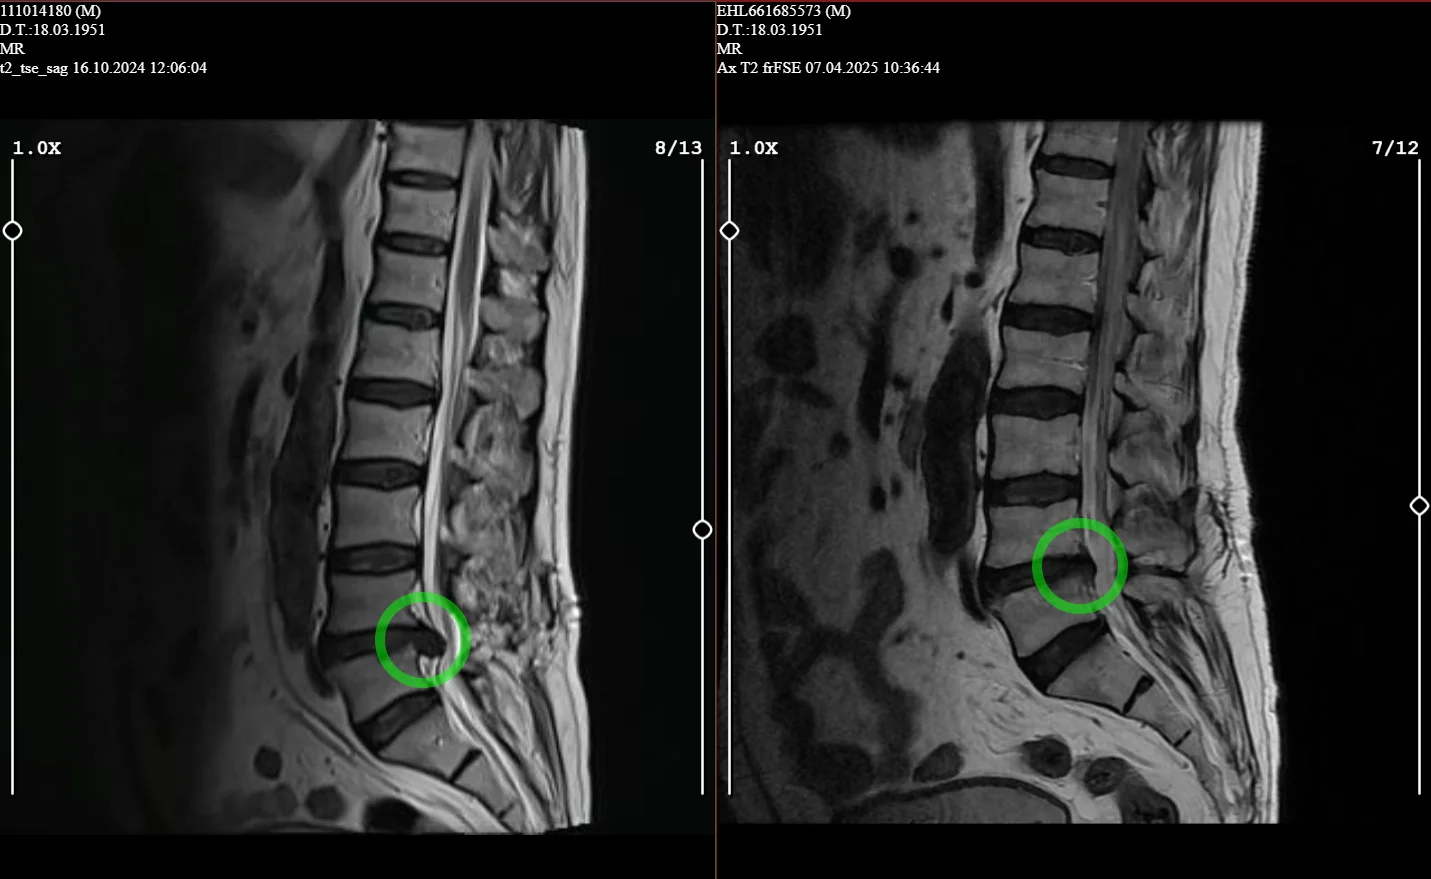

Ameliyatsız Bel Fıtığı Tedavisi

Cerrahi müdahaleye gerek kalmadan bel fıtığına etkili ve güvenli çözümler sunuyoruz

Belde Radyofrekans Tedavisi